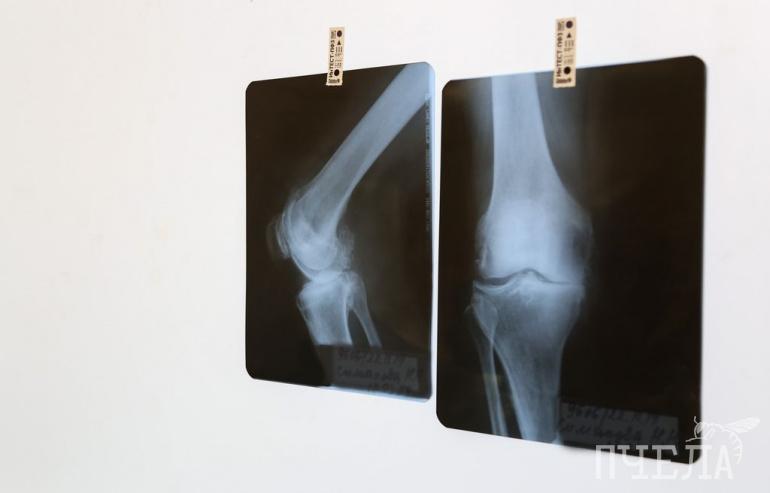

Семь лет назад женщине пришлось перенести несколько операций по замене тазобедренных суставов из-за врожденного заболевания. Хрупкая костная ткань вокруг протеза стремительно разрушалась, в результате чего один из искусственных суставов сместился в мягкие ткани. Доступ к нему оказался перекрыт пучком жизненно важных сосудов.

— Ситуация была тяжёлой вдвойне, так как у пациентки два протеза, — рассказал заведующий отделением травматологии ЧОКБ Леонид Полляк. — Пациентка поступила летом, мы сначала восстановили правую ногу. Там была тяжёлая ситуация, но без грубых анатомических изменений. А слева риски были чрезвычайно высоки — можно было получить осложнения, несовместимые с жизнью: ишемию конечностей, отёк, паралич, тромбоз, вплоть до летального исхода. Потребовалось участие сосудистых хирургов. При отсутствии многопрофильности больницы, скорее всего, не получилось бы так защитить больного от потенциальных неприятностей.

— Это вообще редкая ситуация, но у нас в клинике существует практика, когда мы совместно изучаем снимки, документы и определяем порядок действий, если требуется совместное участие специалистов разного профиля, — объяснил исполняющий обязанности заведующего отделением сосудистой хирургии ЧОКБ Алексей Барышников.